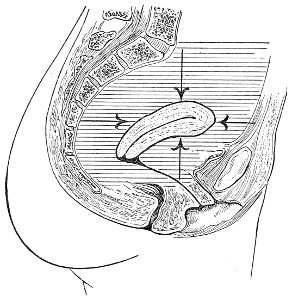

An accurate knowledge of the anatomy and mechanism of the female perineum is essential to an understanding of the nature and treatment of injuries to this structure. The anatomical structures lying between the anus behind and the symphysis pubis in front are those that most directly interest the gynecologist. Proceeding from 57 below upward, we find the following structures lying in superimposed planes: the skin, the superficial fascia, the deep layer of the superficial fascia, the transversus perinæi and the sphincter vaginæ muscles, the anterior layer of the triangular ligament, the posterior layer of the triangular ligament, the levator ani muscle (Fig. 19).

The vagina passes through these structures. They surround and support the ostium vaginæ as the fascia and muscles surround and support the opening of the rectum or the anus. The muscles and fasciæ are attached in the median line between the anus and the vagina, and therefore this part of the body, which is called the perineum, is supported or maintained in its 58 proper position by these various structures. The transversus perinæi arises from the ramus of the ischium and is inserted in the perineum. The bulbo-cavernosus, or sphincter vaginæ, arises in the perineum and is inserted in and about the clitoris. The inner fibers of the levator ani arise from the symphysis pubis and are inserted in the perineum and the lower part of the vagina (Fig. 20). When these muscles contract, their action, therefore, is to draw the perineum upward and forward. At the same time the anus is drawn upward and forward, and so also is the posterior margin of the ostium vaginæ and the lower portion of the posterior vaginal wall.

The vagina has no circular sphincter like the anus, but 59 the vaginal month is kept closed by the action of the transversus perinæi, sphincter vaginæ, and levator ani muscles, which draw the perineum forward, and thus keep the posterior vaginal wall in apposition with the anterior wall.

Fig. 21.—Muscular floor of the pelvis seen from above.

This sling of muscles and fascia, which surrounds and supports the opening of the vagina, may readily be felt in the nulliparous woman by introducing the finger in the vagina and pressing backward and outward toward the ischio-rectal fossa. We then feel plainly, immediately within the ostium vaginæ, a firm resisting band of tissue, apparently about half an inch broad, embracing the posterior portion of the lower vagina. This band is formed by the inner edges of the various muscles and planes of fascia that have been described.

The vagina extends, as a transverse slit in the pelvic floor, upward and backward, approximately in the direction 60 of a line drawn from the ostium vaginæ to the fifth sacral vertebra. It is approximately parallel with the conjugate of the brim, so that when the woman is erect the long axis of the vagina is inclined at an angle of 60° to the horizon. The vagina is not a vertical open tube: it is a slit in the pelvic floor, in health always closed by the accurate apposition of the anterior and posterior walls (Fig. 21). The anterior vaginal wall is about 2½ inches long in a vertical mesial line. The posterior vaginal wall is about 3½ inches long. The vaginal walls are triangular in shape, being broader above than below. The shape of the normal vagina at the pelvic outlet is shown by Fig. 23. The section here shows the vaginal 61 slit of the shape of the letter H. The portions of the slit extending backward and somewhat outward are called the vaginal sulci or furrows. They are directions of diminished resistance in which tears are liable to occur.